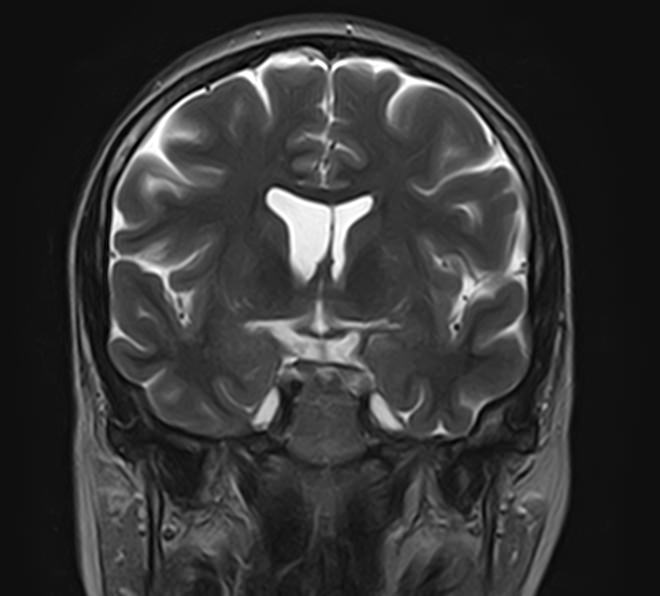

Стандартная МРТ головного мозга дает важную информацию о состоянии и структуре мозговой ткани для выявления большого числа заболеваний, в том числе опухолевых образований, демиелинизирующих заболеваний, воспалительных процессов головного мозга и мозговых оболочек. Стандартную МРТ головного мозга дополняет МР-ангиография, которая отображает состояние артериальной системы кровоснабжения головного мозга. МР-венография головного мозга позволяет детально изучить особенности анатомического и функциональной состояния венозного русла головного мозга.

Компьютерная программа обрабатывает данные, полученные при сканировании, и формирует объемные изображения как самого мозга, так и сосудистой системы в отдельности без прилегающих тканей. Обе методики применяются одновременно и взаимодополняют друг друга, давая полную диагностическую картину.